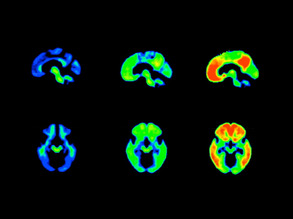

Brain Recipe

18